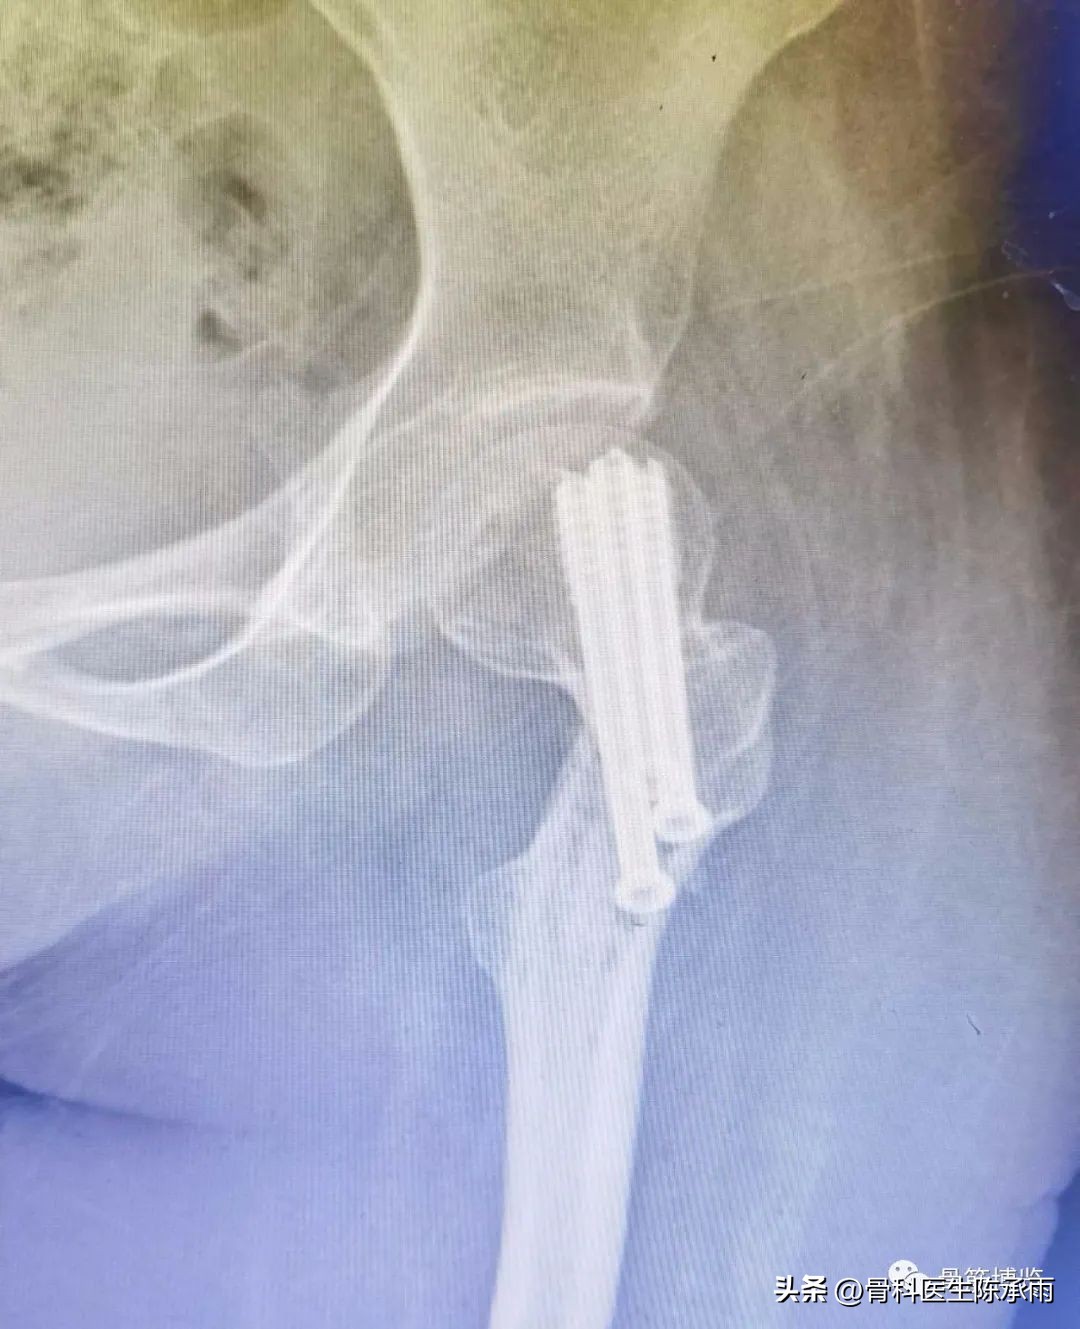

2例

我们这例患者是一位脑瘫患者,患侧肢体短缩细小,股骨颈处及股骨髁上均做过截骨手术,失去了正常的角度,且股骨颈较细。给手术带来不小的难度。

术前尝试闭合复位,效果满意,决定行经皮穿钉,但股骨颈角度不正常,颈部细小,很难容得下3枚直径7.3空心钉,最后1枚空心钉部分切出股骨颈上缘。

术后拍片由于患肢内旋畸形,未显示标准正位

6个月后复查

患者行走如受伤前,无疼痛,无明显不适